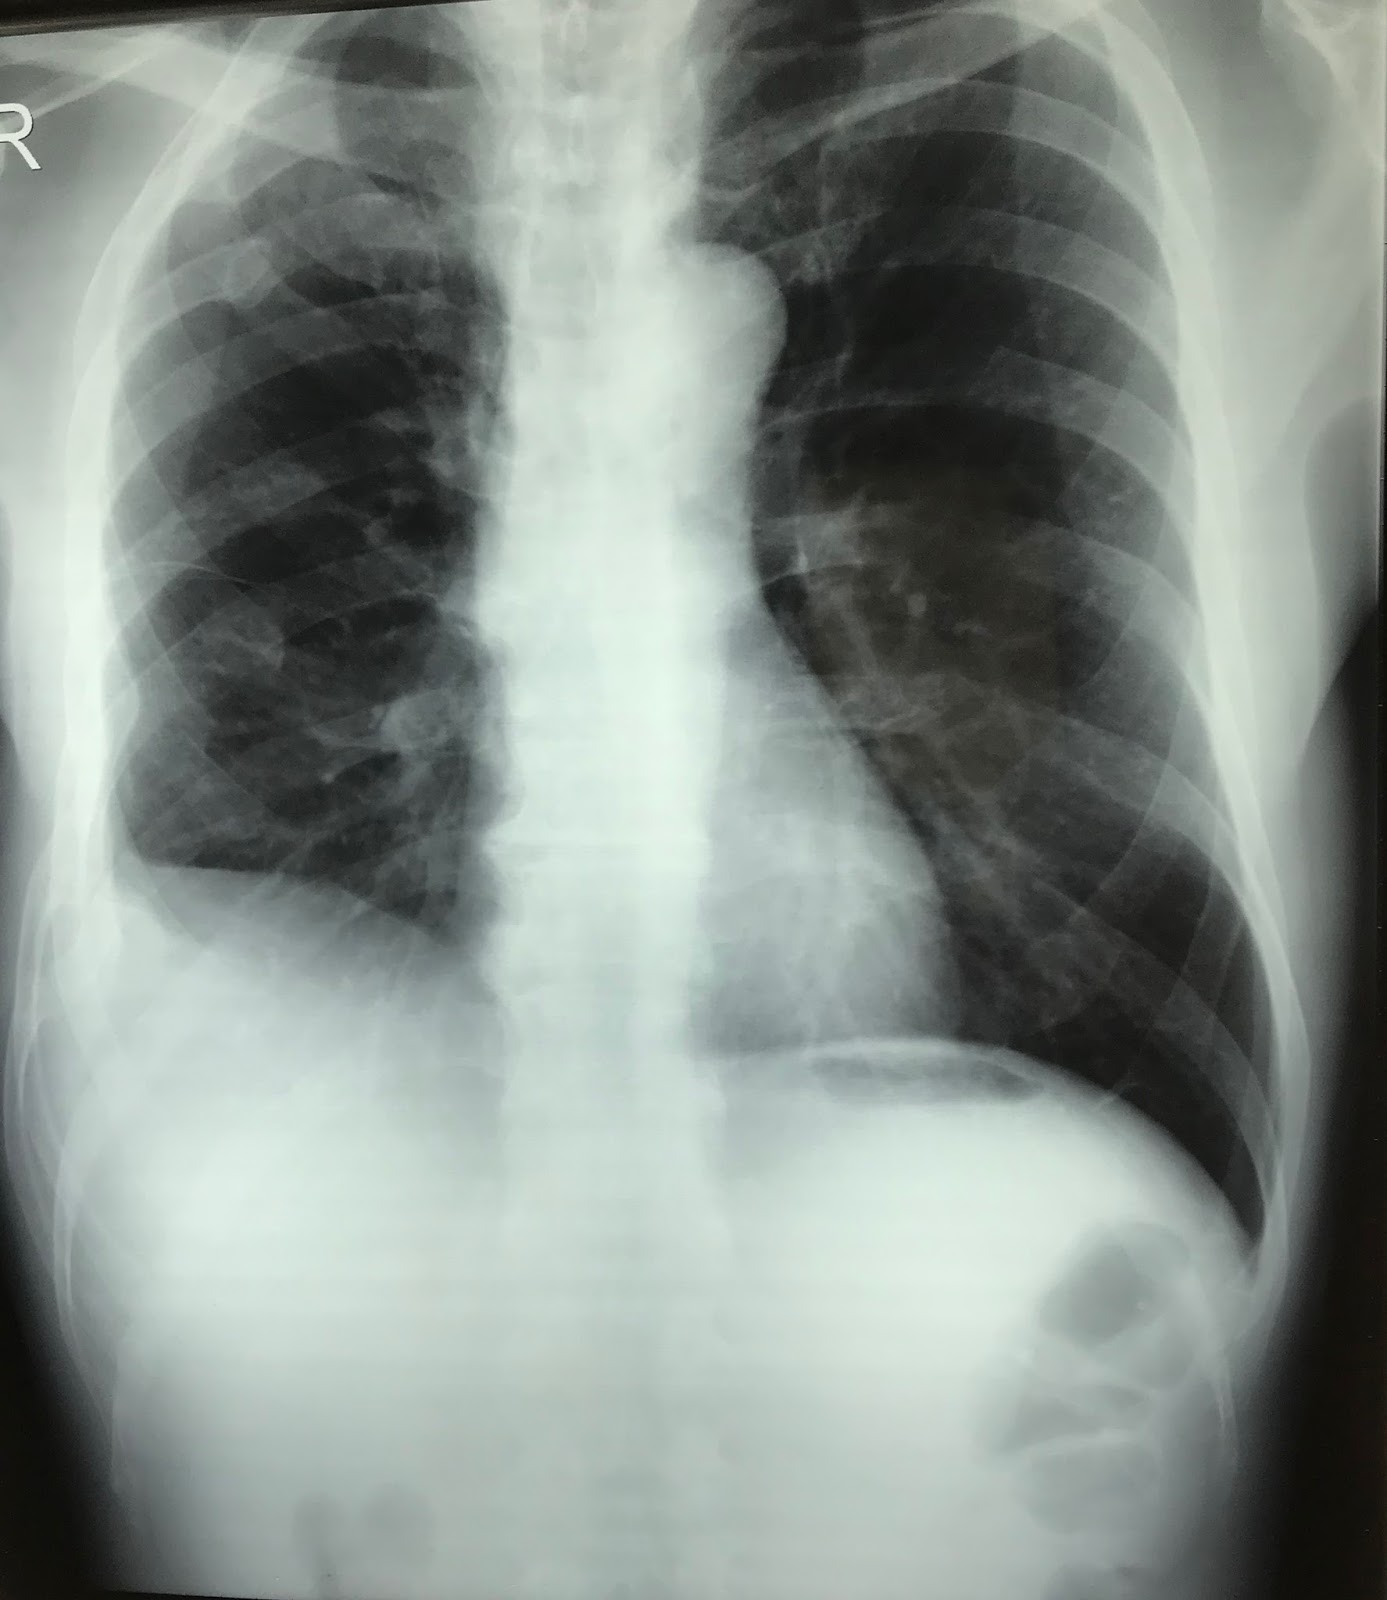

Splenomegaly radiograph Radiology at St. Vincent's University Hospital Can Chest X Ray Detect Spleen Your doctor can often feel it by gently examining your left upper belly. Its presence may indicate fats and other substances in your vessels, damage to. Plain radiographs are of use when they show the spleen against a background of gas in the fundus of the stomach and. Web an enlarged spleen is usually detected during a physical exam. Splenomegaly. Can Chest X Ray Detect Spleen.

Splenic incidentaloma on routine chest radiography before admission to Can Chest X Ray Detect Spleen However, it may also refer to an enlarged spleen detected. Web an enlarged spleen is usually detected during a physical exam. On all these imaging modalities, splenosis shows the same. Web us, ct and mr imaging can be used to detect splenosis. We can see rib fractures in the left lower chest which can. Its presence may indicate fats and. Can Chest X Ray Detect Spleen.